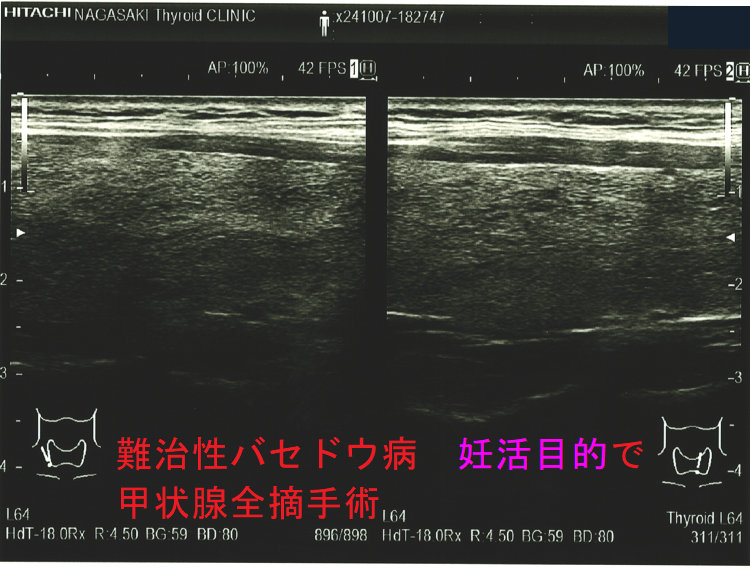

難治性バセドウ病 妊活目的で甲状腺全摘手術1

難治性バセドウ病 妊活目的で甲状腺全摘手術標本 超音波(エコー)画像 (水平断)